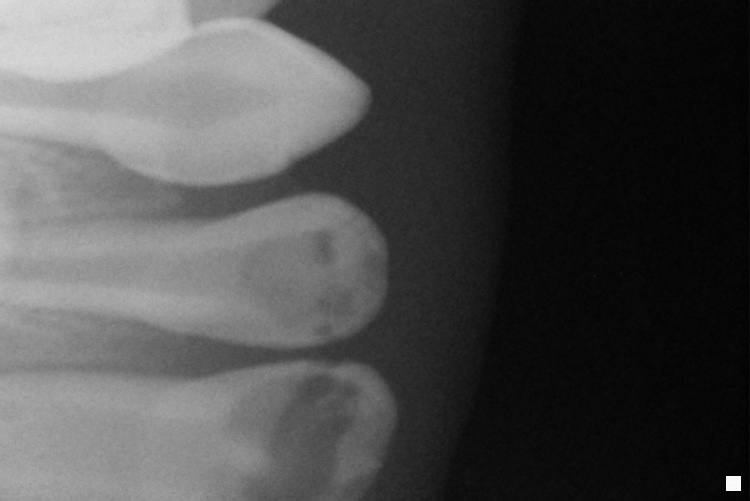

IO000001.jpg

2020-07-28 13:45 67K